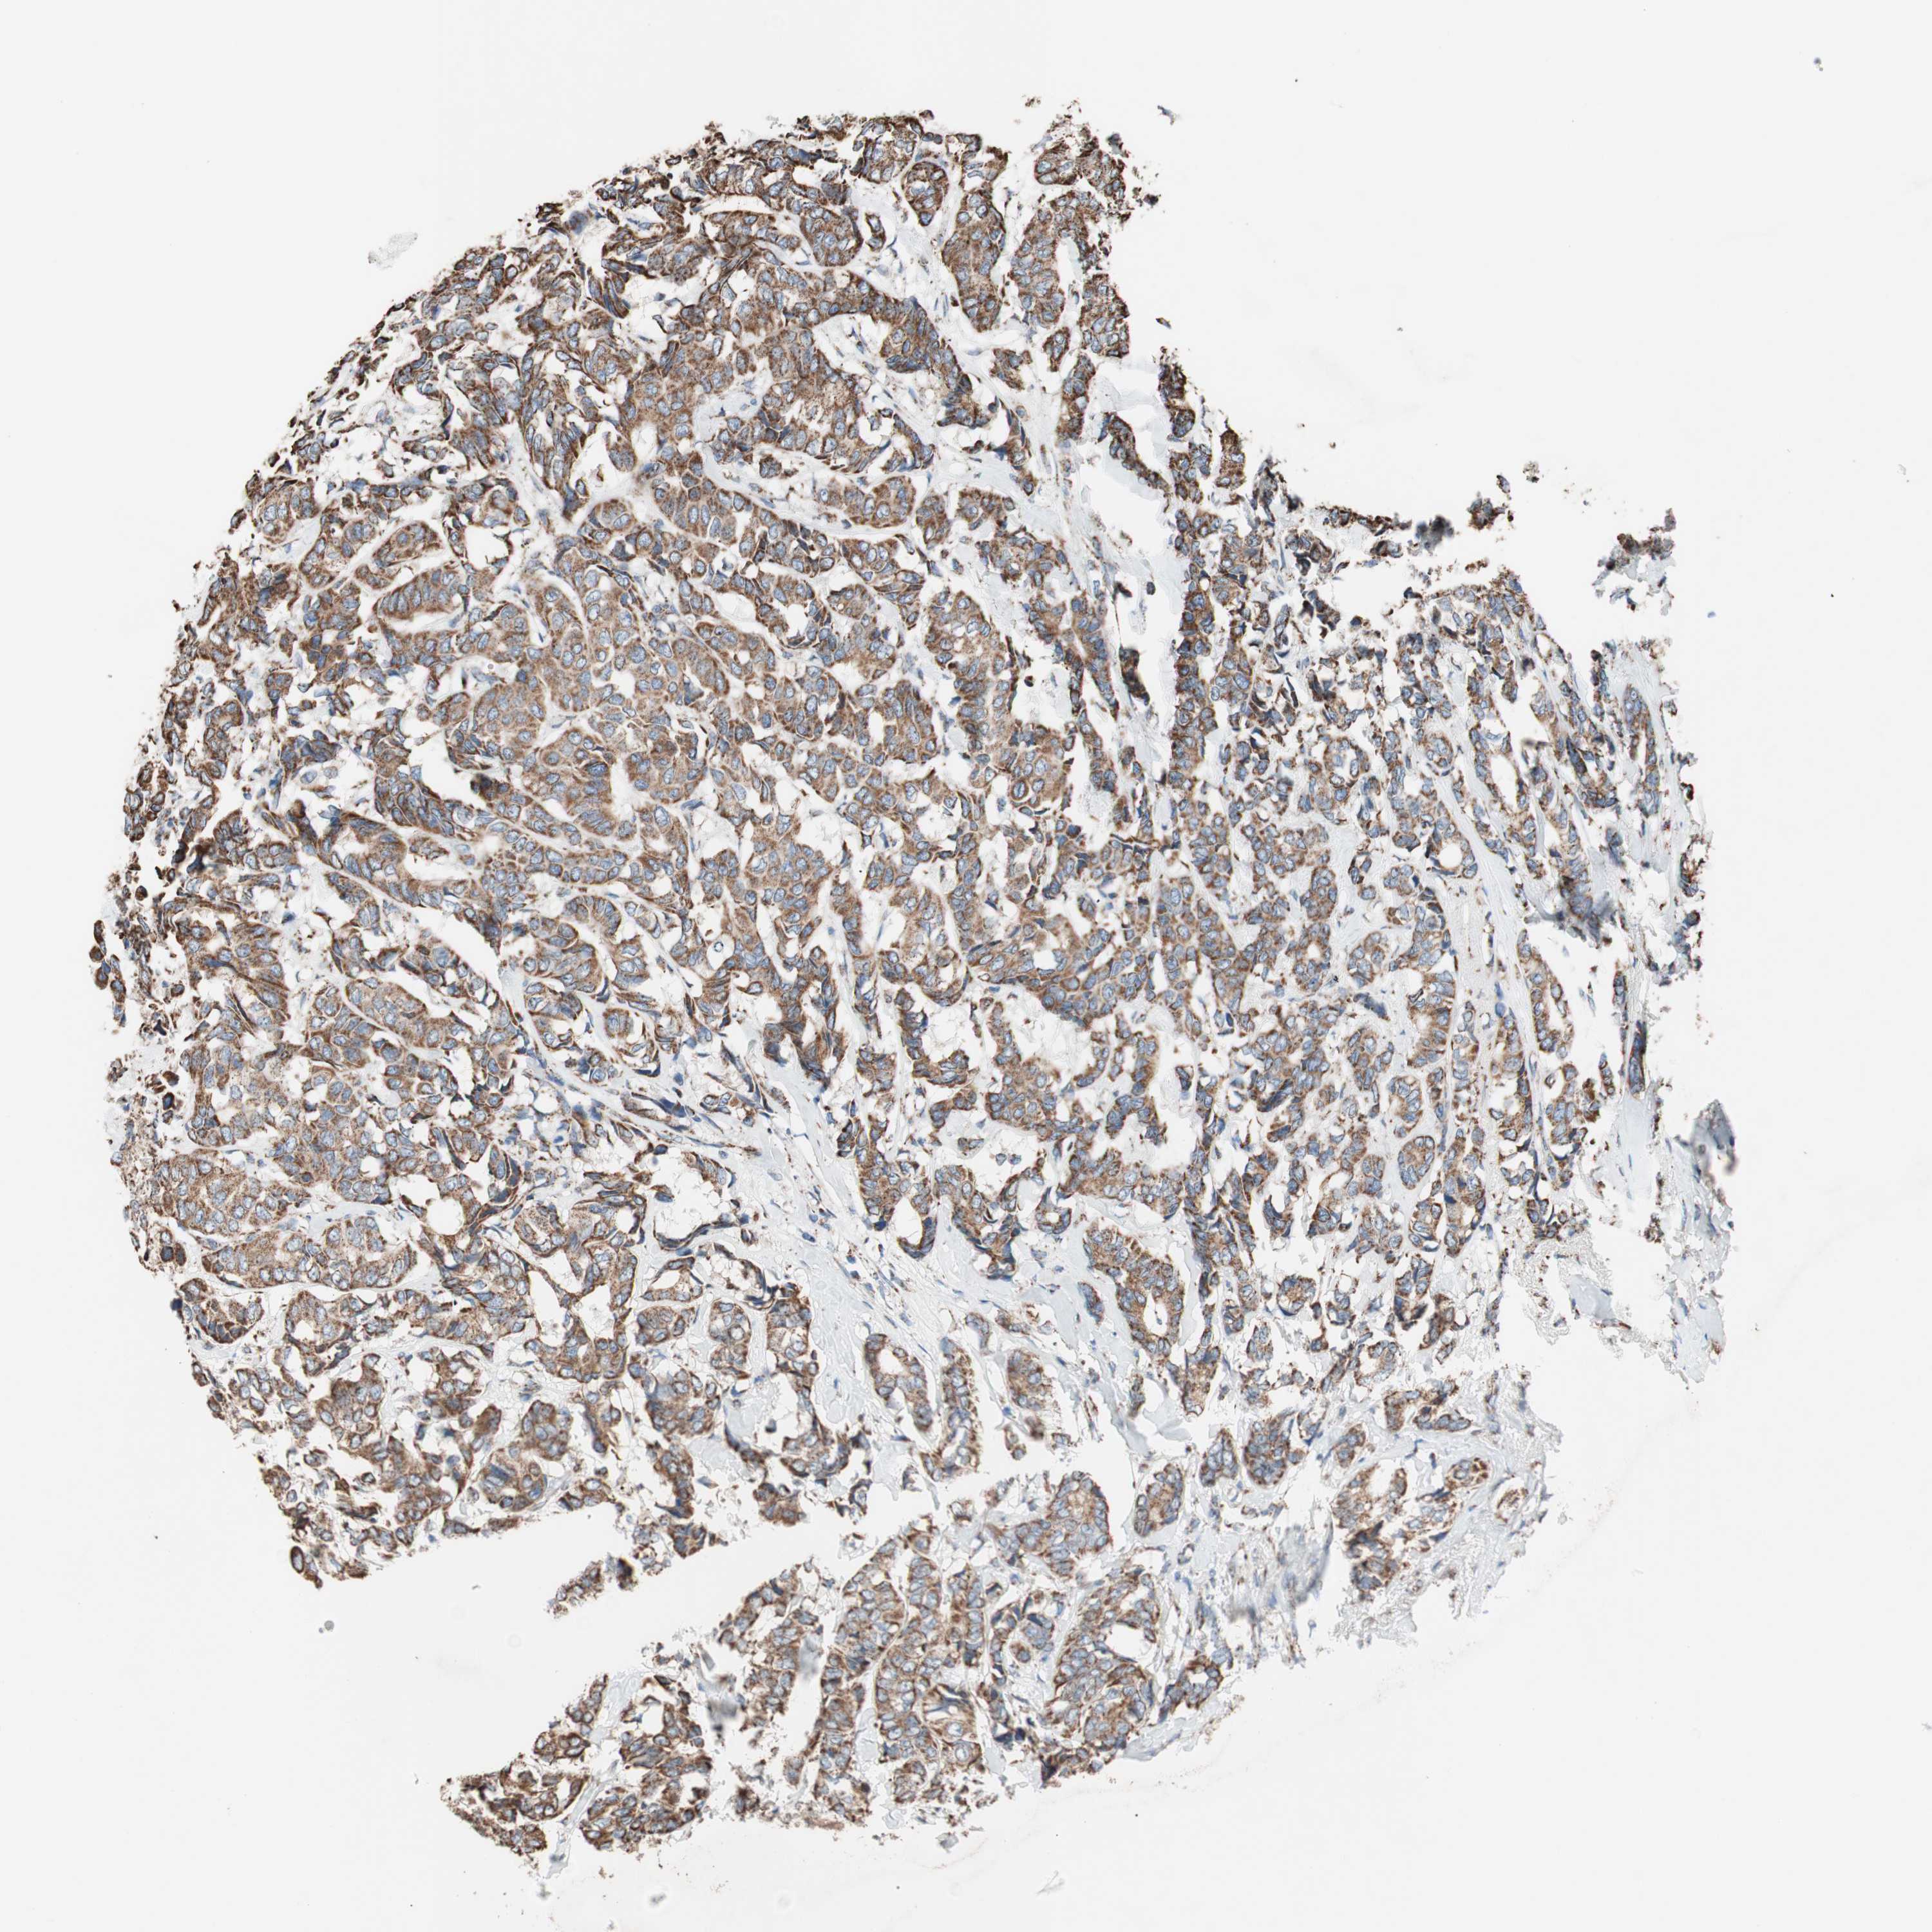

CANCER BREAST CANCER Show tissue menu

BRCA TCGA BRCA VALIDATION PROTEIN EXPRESSION

ANTIBODIES

AND

VALIDATION